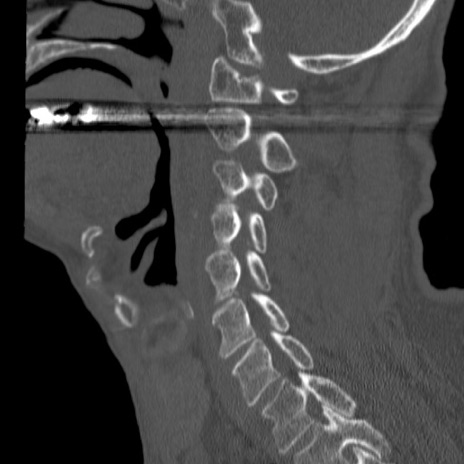

症例46 頚椎CT(矢状断像)

【症例】80歳代男性

【主訴】両側頚部〜上肢のしびれ

【現病歴】昨日、自宅内で転倒、その後より上記症状あり。意識障害なし。

【身体所見】両側上肢のallodynia(熱痛覚過敏)あり。MMTおよびDTRは正確な所見取れず。両上肢の挙上はなんとか可能。

異常所見と診断は?